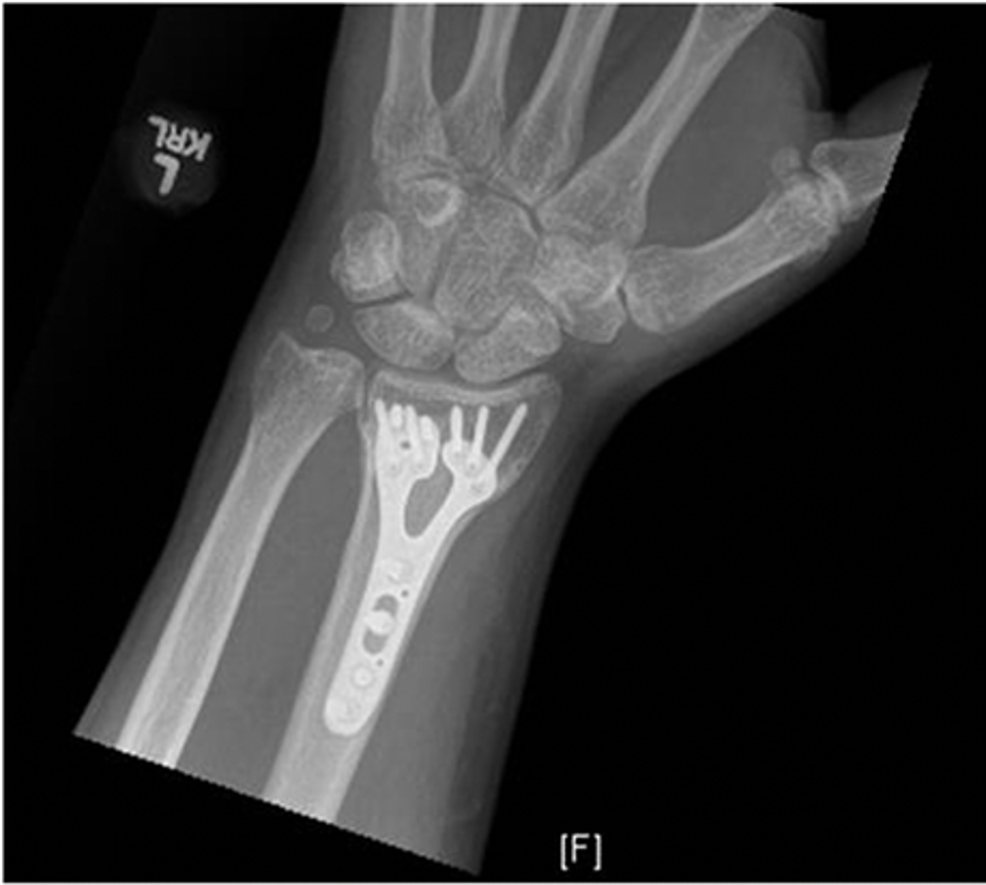

10 Facts To Know About Your Wrist Fracture Procedure Rothman

From rothmanortho.com

10 Facts To Know About Your Wrist Fracture Procedure Rothman Heat After Wrist Surgery This leaflet is designed to guide you through the recovery process after your recent operation. Web both heat treatments and cold treatments are inexpensive and extremely effective modalities that can help speed up recovery and. Web it is recommended that you exercise your wrist as soon as you can after your cast or splint has been removed. Web wrist surgery. Heat After Wrist Surgery.